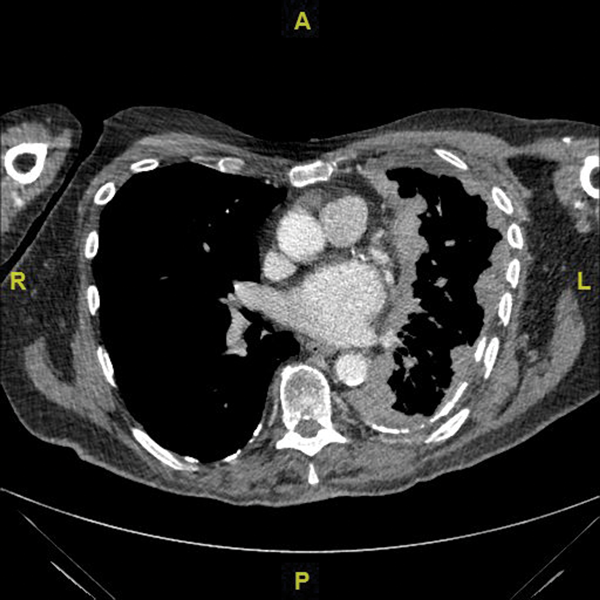

Where there is a suspicion of MPM, the BTS recommends investigation with a contrast enhanced CT scan with intravenous contrast timed to enhance the pleura.2 Figure 1, shows malignant mesothelioma, with concentric pleural thickening extending over the mediastinal surface.

IPCs are also recommended for management of a trapped lung. This occurs when pleural infiltration prevents lung re-expansion following drainage of pleural fluid, meaning talc pleurodesis is unlikely to succeed due to reduced parietal and visceral pleural contact (see figure 2).11